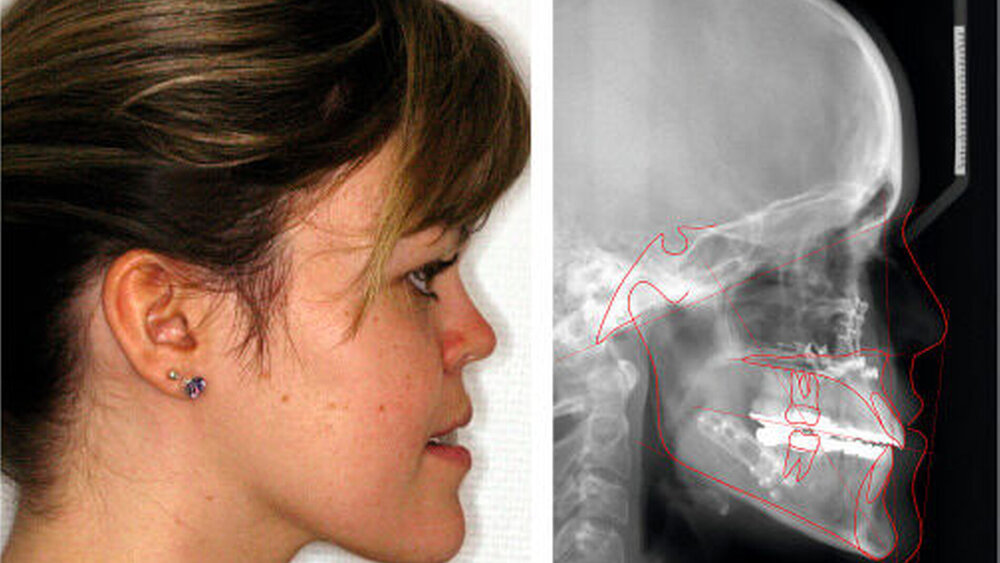

Die Planung der bimaxillären Umstellungsosteotomie erfolgte mittels Modell-Operation und Simulation am Fernröntgenseitenbild (fr-win, Computer konkret, Falkenstein) (Abbildung 5).

Die Maxilla wurde intraoperativ 3 mm vorverlagert, 3 mm posterior impaktiert und transversal 2 mm erweitert. Die Mandibula wurde mittels sagittaler Spaltung nach Obwegeser/Dal Pont 4 mm rückverlagert. Abbildung 6 zeigt den postoperativen Befund am Fernröntgenseitenbild und von extraoral lateral.